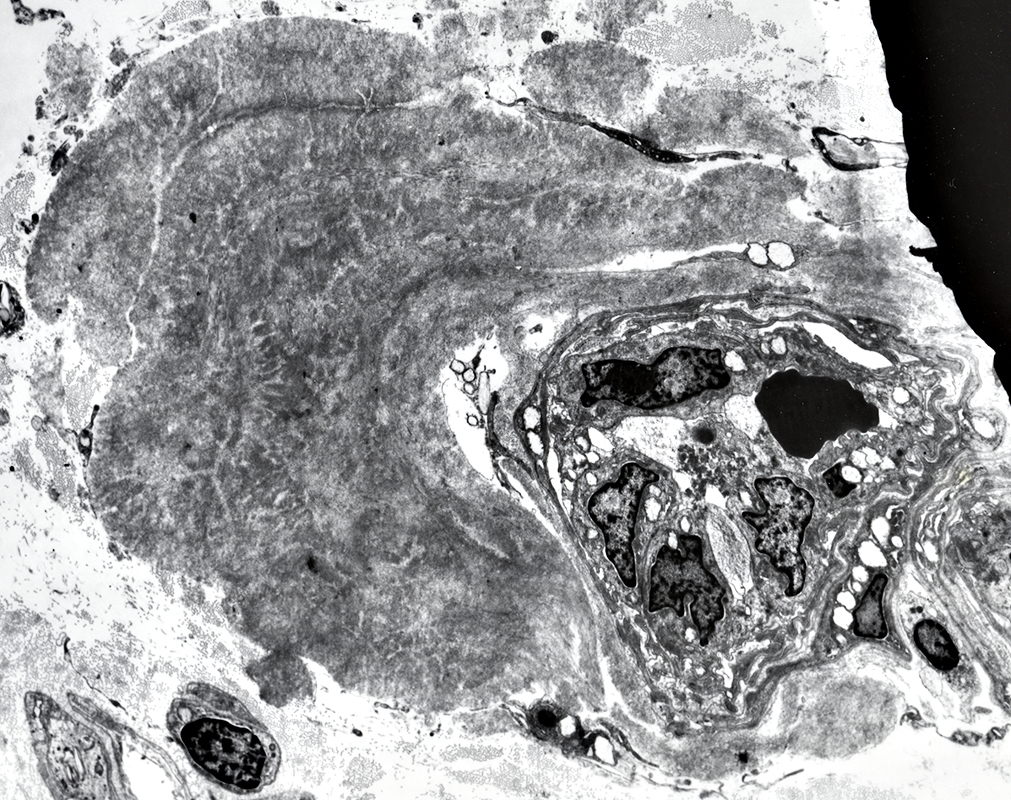

Amyloid

Around wall of endoneurial microvessel

Asymmetric deposits

Replaces basal lamina of endoneurial microvessel

Surrounds endoneurial microvessel

Amyloid: Fibrils

Typical widths

TTR: 6 to 8 nm

Imunoglobulin light chain: 10 to 20 nm